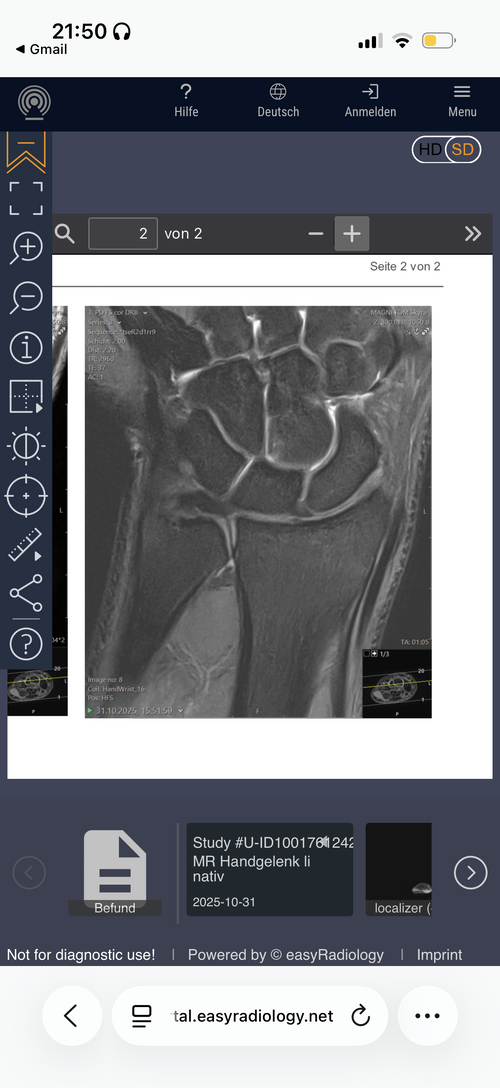

Are my growth plates closed and if not how much growth would hgh + ai help me grow?

Attachments

• IMG_0429.png

IMG_0429.png

Your hands won’t grow, this dosent mean your legs growth plates are closed tho.